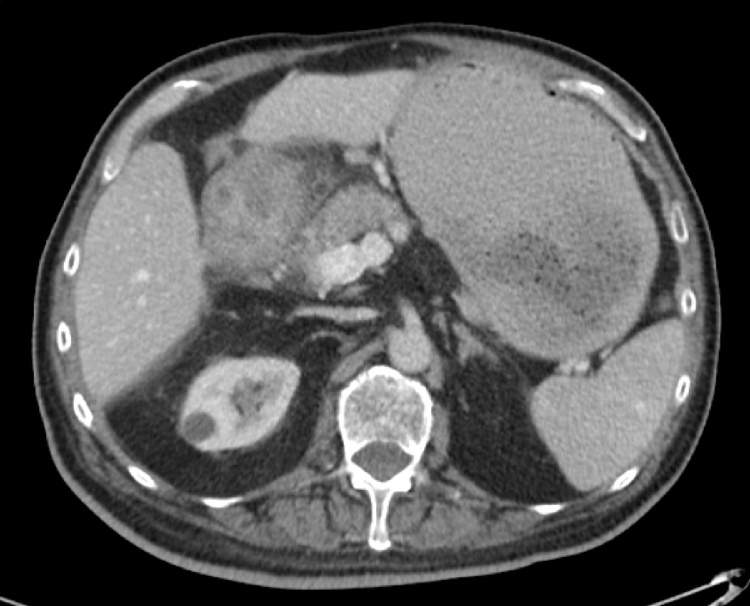

An 80-year-old male presented to the General Surgery clinic for symptoms consistent with gastric outlet obstruction. He had been seen in the clinic five years previously due to biliary disease requiring a laparoscopic cholecystectomy. The patient was currently reporting a 4-month history of 30-pound weight loss, progressively worsening nausea, vomiting and significant gastroesophageal reflux. He had already been seen by a gastroenterologist who arranged for esophagogastroduoenoscopy (EGD) and computed tomography (CT) of the abdomen. EGD found retained gastric contents, with thickening of the pylorus and first part of the duodenum; biopsies taken were negative for malignancy. The CT demonstrated bulky, circumferential and irregular thickening and enhancement of the gastric wall at the level of the pylorus, involving the duodenal bulb (Fig. 1). The differential at the time included peptic ulcer disease, primary gastric neoplasm, infectious disease, or lymphoma.

Fig. 1.

Axial view of CT abdomen/pelvis with IV contrast demonstrating a bulky circumferential irregular thickening and enhancement of the gastric wall at the level of the pylorus involving the duodenal bulb. Additionally, there is a chronic ellipsoid pocket of fluid associated with the peritoneal lining posterior to the liver that was noted to represent an old abscess or hematoma cavity.